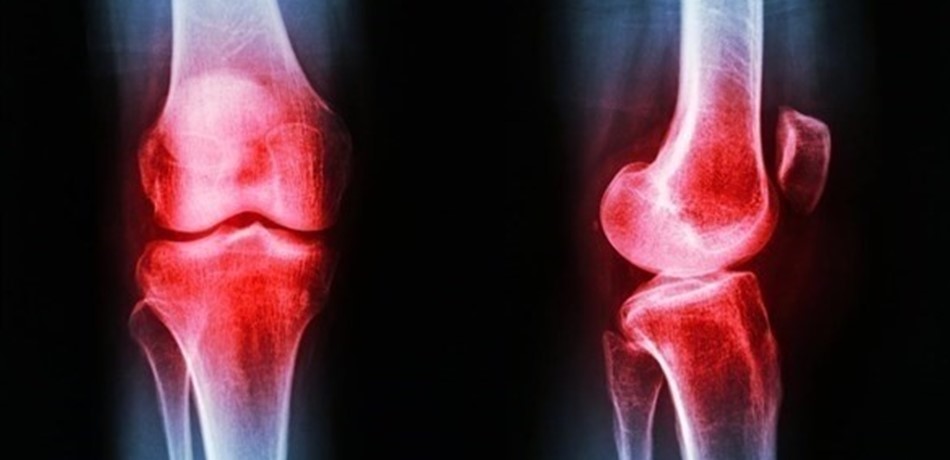

إحذروا.. حقن الكورتيزون للمفاصل يؤذيكم!

قالت نتائج دراسة جديدة إن مرضى التهاب مفاصل الركبة لا يستفيدون من حقن الكورتيزون التي يتم حقنهم بها كل 3 أشهر كما يُعتقد. ووجد الباحثون أن الحقن قد تؤدي إلى تآكل الغضروف خلال السنتين التاليتين لتعاطيها. أجريت أبحاث الدراسة في مركز تافتس الصحي ببوسطن، ونُشرت نتائجها في مجلة "جاما". وتوصلت نتائجها إلى توصيات بعدم إعطاء مرضى مفاصل الركبة حقن الكورتيزون. وتصاب مفاصل الركبة بالالتهاب نتيجة تشقق الغضروف، وهو أنسجة تحمي أطراف عظام المفاصل من الصدمات وتعمل كوسادة لتخفيفها. وكانت دراسات سابقة قد حثّت على إعطاء حقن الكورتيزون لتخفيف آلام هذا الالتهاب، لكن تم تتبع مجموعة من المرضى الذين أعطيت لهم الحقن كل 3 أشهر لمدة سنتين، وتبين أن من تأثيراتها تآكل الغضروف ونقص كثافته، ما يجعله أكثر عرضة للالتهاب والتشقق. وبشكل عام، أظهرت النتائج أنه حتى في حالة عدم تضرّر الغضروف لا ينبغي إعطاء حقن الكورتيزون لأنها لا تحقق فائدة لمرضى التهاب مفاصل الركبة.